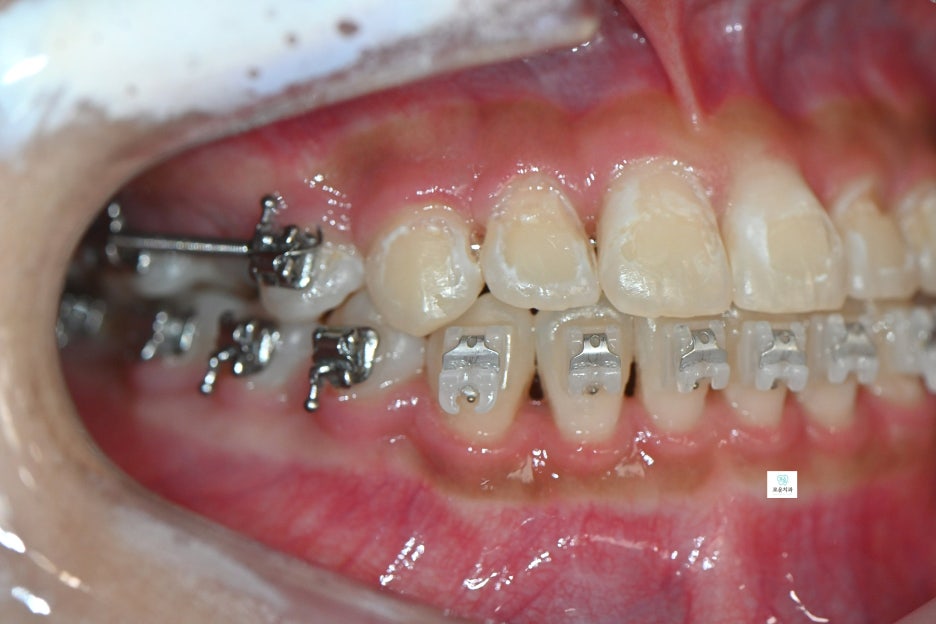

“교정 중 발생한 앞니 사이 충치 치료 사례”

장기간 교정 치료를 진행 중이던 환자분으로

앞니 사이 충치가 발견되어 치료를 위해

내원하셨습니다.

앞니에 생긴 우식은 치아 4개에 사이에 생겨 총 6면의 우식이 발생

→ 치아는 붙어 있는 면 양쪽으로 우식 진행되기 때문에 면수로 진행

첫 방문에서는 검진을 통해

치료 부위를 확인하였고,

두 번째 방문에서는 교정치과와 일정 조율 후

와이어를 제거한 상태로 내원하여

치료를 진행했습니다.